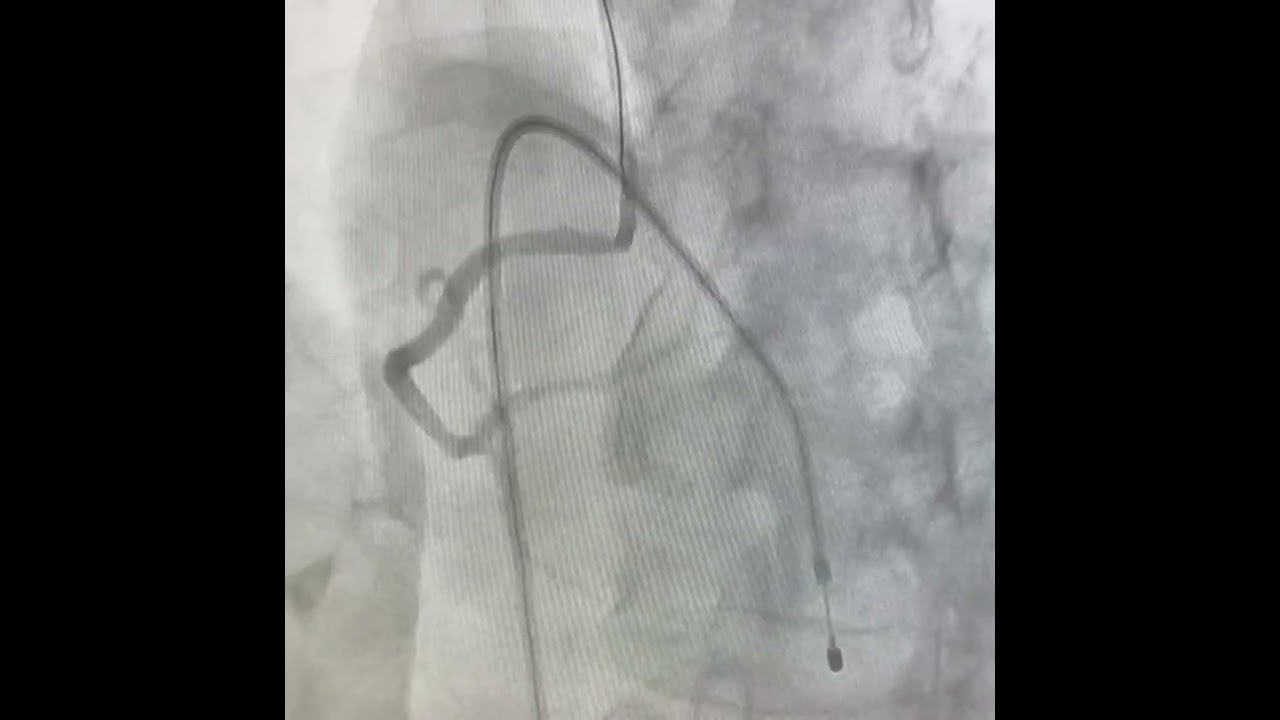

Cardiología Intervencionista y Clínica

Atención integral para la salud de tu corazón

Chequeo Cardiovascular Integral

Incluye:

Consulta médica

Electrocardiograma

Interpretación de estudios previos

Plan de prevención personalizado

Todo en una sola cita, con atención profesional y tecnología de alto nivel.